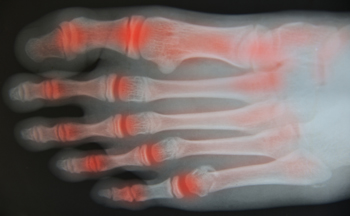

What Are the Early Signs of Foot Arthritis?

Do I need an x-ray?

Yes. If you are suffering from foot or ankle pain, our doctor will need an x-ray to identify possible fractures. Without an x-ray, it is impossible to determine whether a fracture exists.